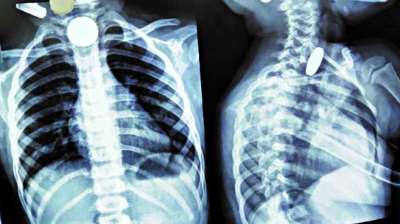

खिलौना नहीं सिक्का था! बच्चे ने निगले 5-10 रुपये के सिक्के, डॉक्टरों ने ऑपरेशन कर निकाले

24 Jul, 2025 04:09 PM IST | STATEBREAKING.COM

दिल्ली : दिल्ली के एक सरकारी अस्पताल के डॉक्टरों ने 12 वर्षीय बच्चे की जान बचाई है। बच्चे ने पांच और दस रुपये के तीन सिक्के निगल लिए थे। सिक्के...